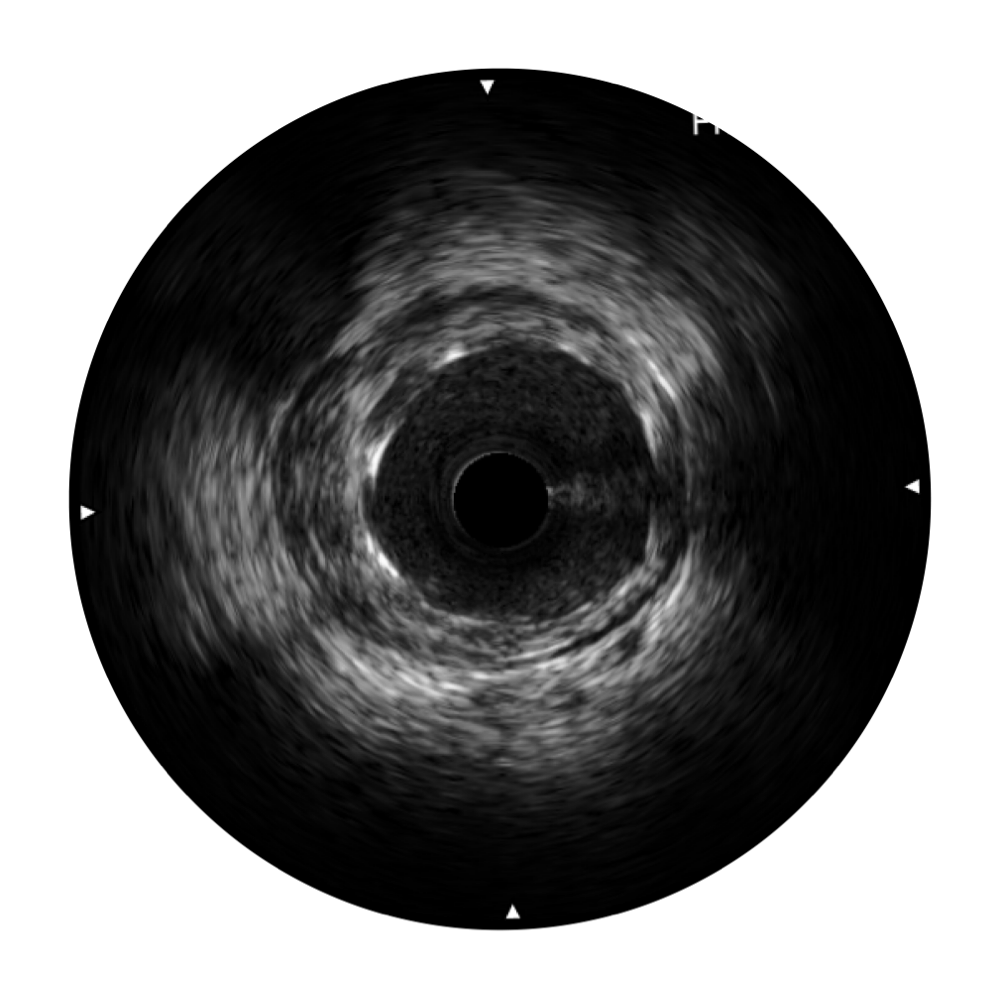

血管内超声(IVUS) 通过对病变程度、性质和累及范围的精确判断,可帮助选择治疗策略和方法,指导介入治疗过程,能够降低主要不良心血管事件,改善预后,在复杂病变介入治疗中用于指导支架置入的优势更为明显。血管内超声(IVUS)已成为精准心血管介入治疗的“金标准”。

1xBET始终关注未满足的临床需求:超宽频成像技术同时提供高清分辨力和充足穿透深度,适应不同血管结构的治疗引导;智慧赋能,简化操作,降低临床应用难度和缩短学习曲线。

对比传统IVUS导管成像,1xBET宽频IVUS图像的近场支架梁显影更细腻,远场中膜外血管仍清晰可辨,兼顾远中近,兼顾分辨力与穿透深度